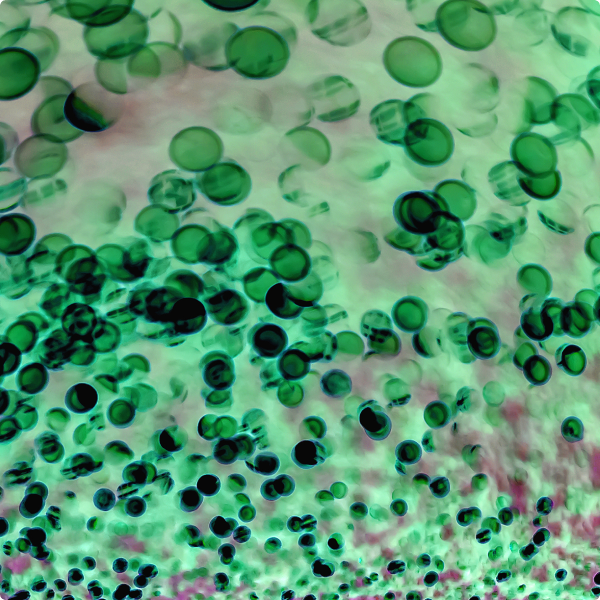

The spectrum of these microorganisms is diverse, and these tiny invaders aren't just passive bystanders; they're capable of forming slimy biofilms within the waterlines, where they flourish and multiply. This biofilm can harbour and protect these microorganisms, rendering them more resilient and challenging to eliminate.

Bacteria: These single-celled organisms are the most common inhabitants of dental unit waterlines. Among them are opportunistic pathogens like Legionella, Pseudomonas, and Mycobacterium. These bacteria can multiply rapidly within the moist environment of the waterlines, forming biofilms that provide protection against disinfection efforts.